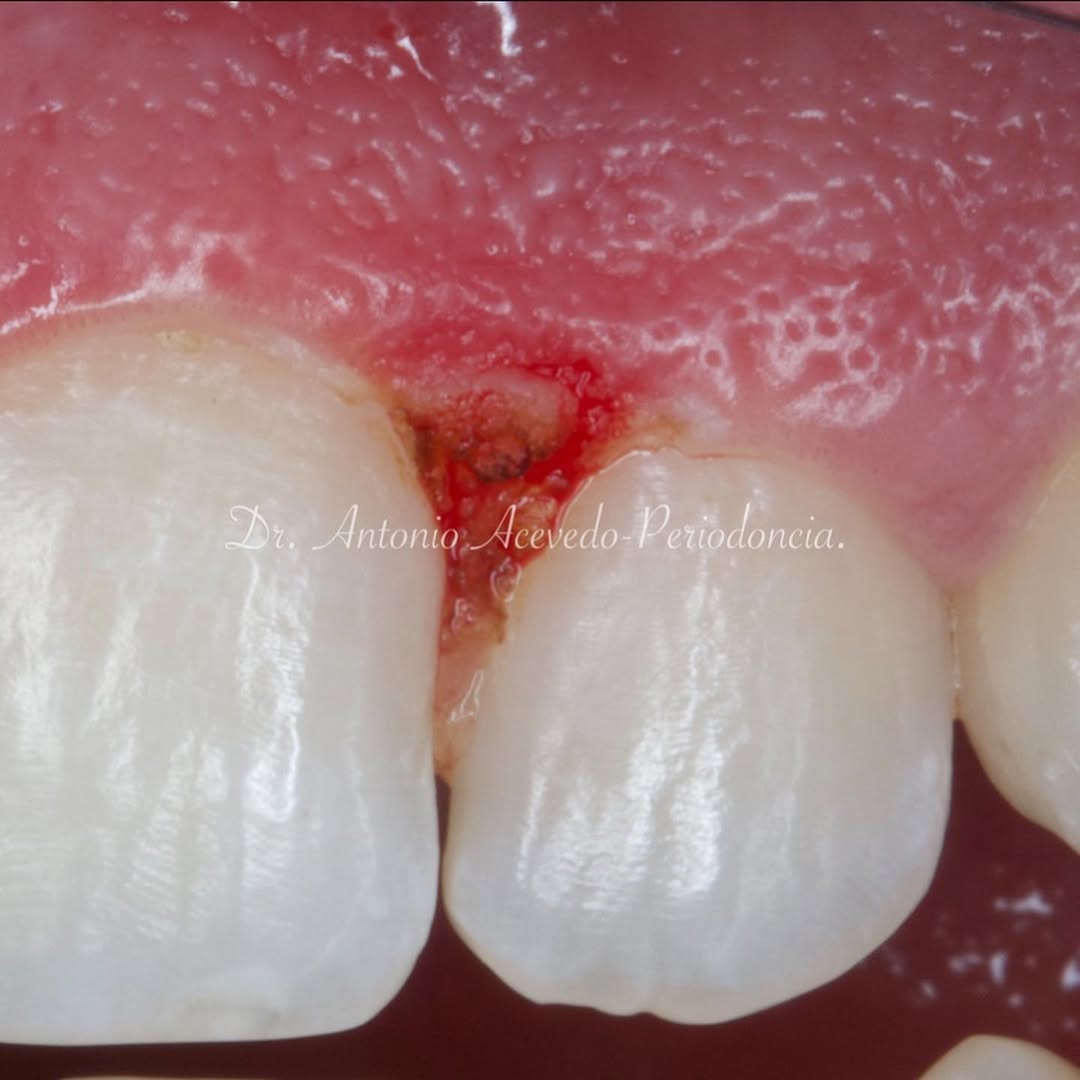

El curso comenzará con la presentación del caso clínico que se abordará durante la formación, seguida de una cirugía en directo. A lo largo de la jornada se desarrollarán conceptos biológicos aplicados a la regeneración ósea, la exposición de casos clínicos centrados en la regeneración

La formación comenzará con la presentación del caso clínico que se abordará durante el curso, seguida de una cirugía en directo, que permitirá observar paso a paso el procedimiento y la toma de decisiones clínicas. Durante la jornada se profundizará en los conceptos biológicos aplicados a

Una jornada centrada en la teoría paso a paso y en la observación de dos cirugías en directo, diseñada para profundizar en la regeneración ósea con técnica Khoury y en la reentrada con colocación de implantes.

Durante la formación se desarrollará la teoría paso a paso de la técnica de